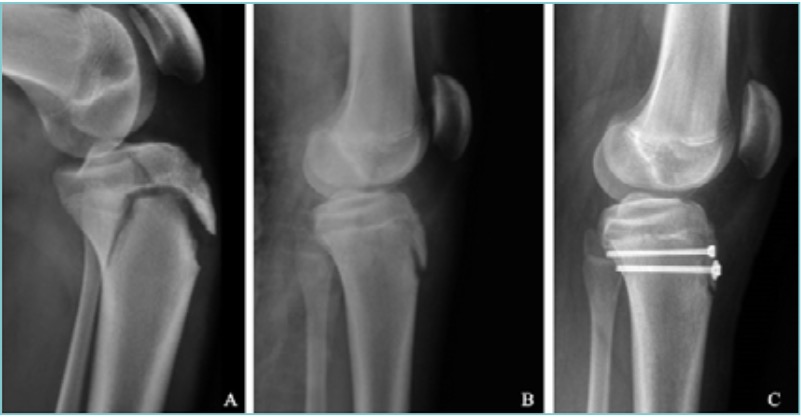

Seppur non presentando caratteri di urgenza (a meno di disturbi neuro-vascolari associati), i distacchi condro-epifisari devono avere preferibilmente un trattamento non dilazionato oltre le 48 ore 7. Il trattamento nei distacchi condro-epifisari composti prevede la sola tutela in apparecchio gessato. Nei distacchi condro-epifisari scomposti è invece necessaria una precoce riduzione mediante trazione prolungata e manovre delicate, preferibilmente in narcosi, cercando di ottenere per quanto possibile il ripristino dell’anatomia epifisio-metafisaria. Manovre di riduzione forzate o tentativi ripetuti di riduzione devono essere evitati per il rischio di danneggiare la fisi. In alcuni casi è utile la trazione transcheletrica con filo di Kirschner che è d’aiuto nelle manovre di riduzione e nella contenzione della frattura in gesso. Gli spostamenti secondari in gesso sono rari ma l’immobilizzazione va mantenuta per 25-30 gg. Nelle lesioni non riducibili si ricorre invece alla riduzione cruenta e alla sintesi di minima con fili di Kirschner di piccolo diametro o viti. I mezzi di sintesi per la fissazione interna devono essere posizionati in modo da rispettare il più possibile l’integrità della fisi. Quando la geometria della frattura lo consente i mezzi di sintesi devono essere posizionati paralleli al piano di accrescimento (Fig. 1). Quando invece la frattura non lo consente e i mezzi di sintesi vengono posizionati transfisari, si deve evitare la compressione e, se residuano più di 2 anni di crescita, l’impianto transfisario deve essere rimosso una volta guarita la frattura 8. È tuttavia utile ricordare che un attraversamento temporaneo e non superiore al 30% della fisi da parte di mezzi di sintesi può non causare l’arresto della crescita.